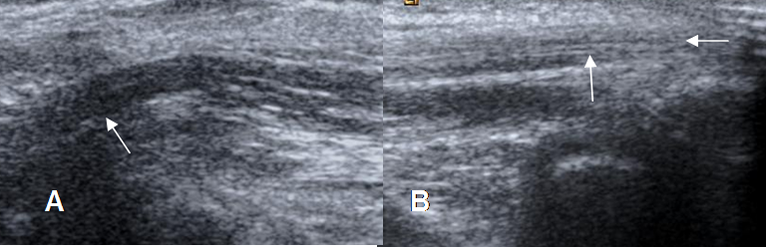

Fig 16. Tendones normales en ecografía.

A: Vista longitudinal, en el origen de los flexores.

B: Origen de los extensores, en vista longitudinal.